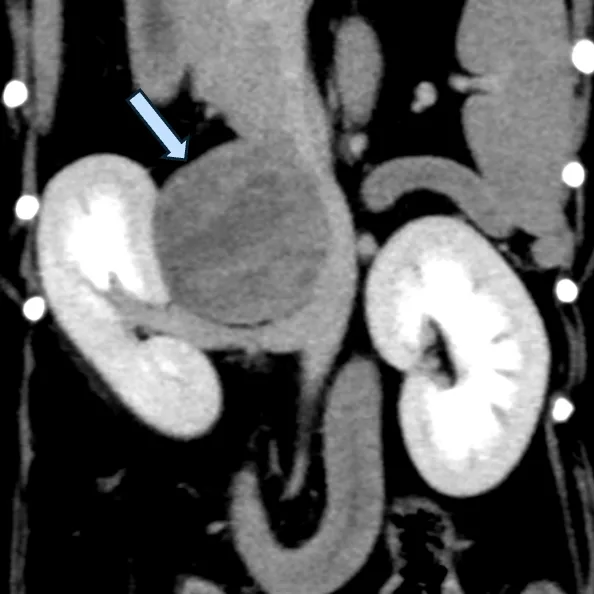

CT検査

・腫瘍のサイズ、血管との関連性を評価します。

・下垂体や腫瘍の転移がないかも同時に評価します。

・外科治療を行う場合には必須の検査となります。

悪性所見には、副腎腫瘍サイズが2cm以上、血管内浸潤、転移があります。

*画像提供:松原動物病院